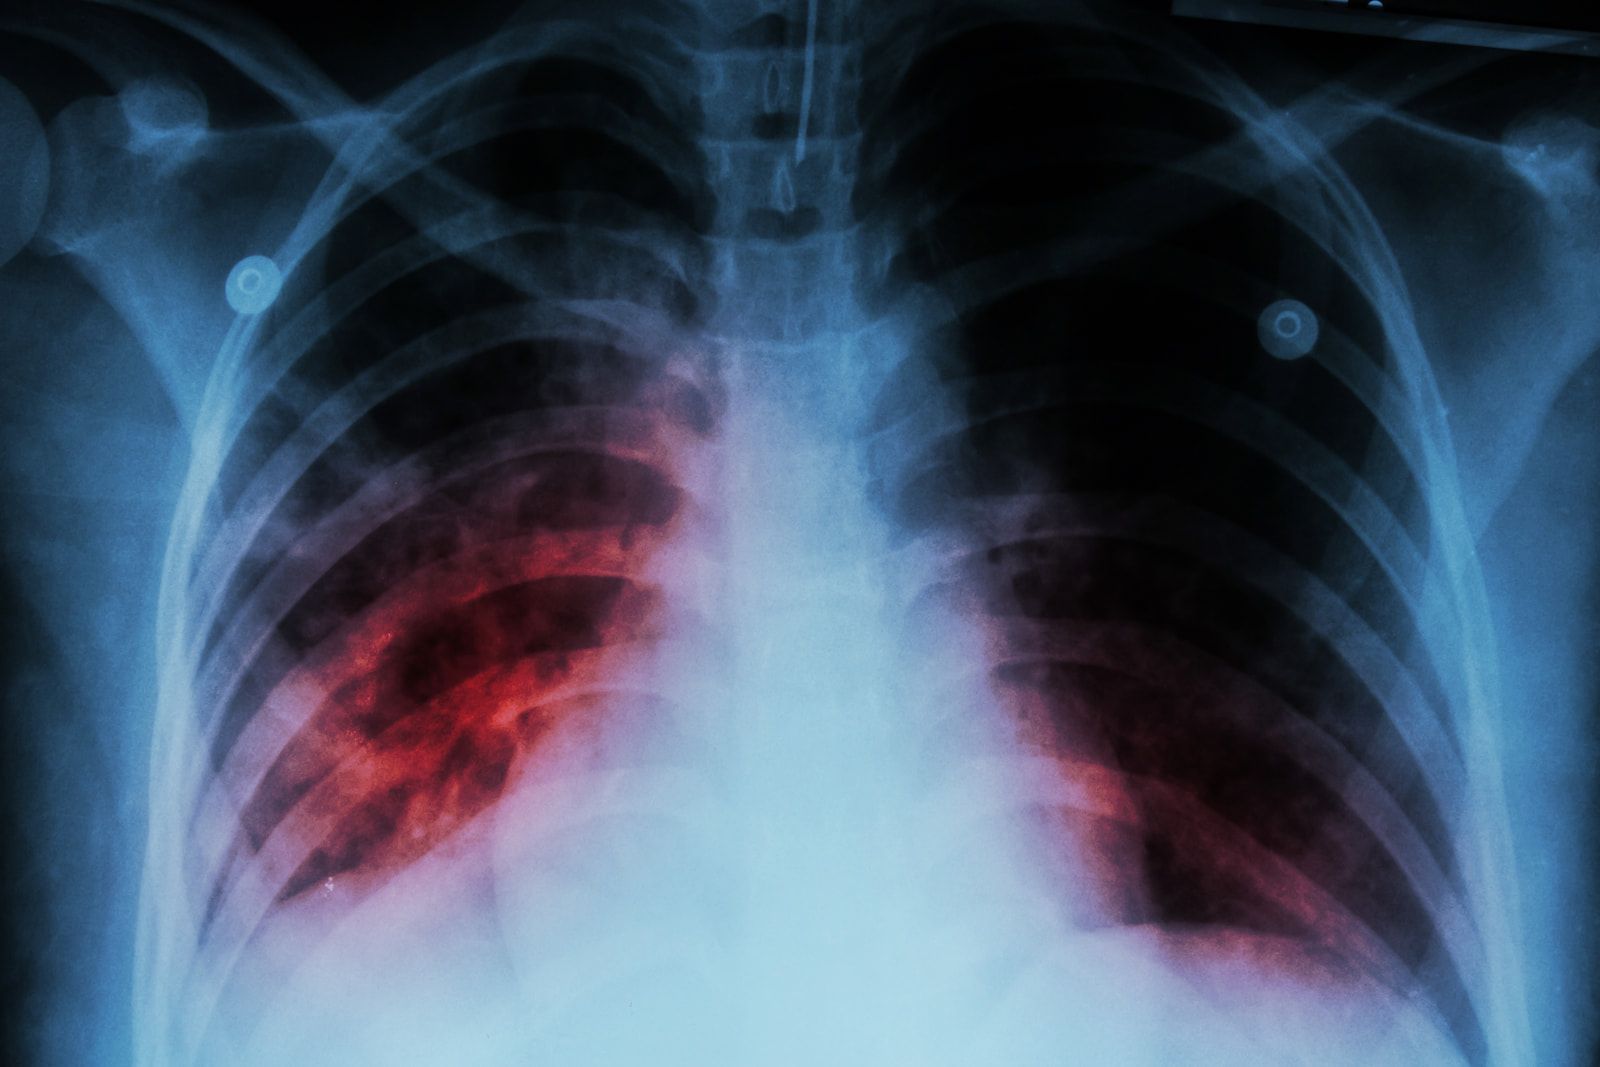

The fight against Tuberculosis (TB) has been marked by a glaring absence: a modern, effective vaccine. While TB continues to exert a heavy toll, claiming 1.6 million lives in 2021 and affecting over 10.6 million individuals, the medical community has been relying on the century-old Bacille Calmette-Guรฉrin (BCG) vaccine. Its limited protection, especially against pulmonary tuberculosis in adults and adolescents, underscores the urgency of the situation.